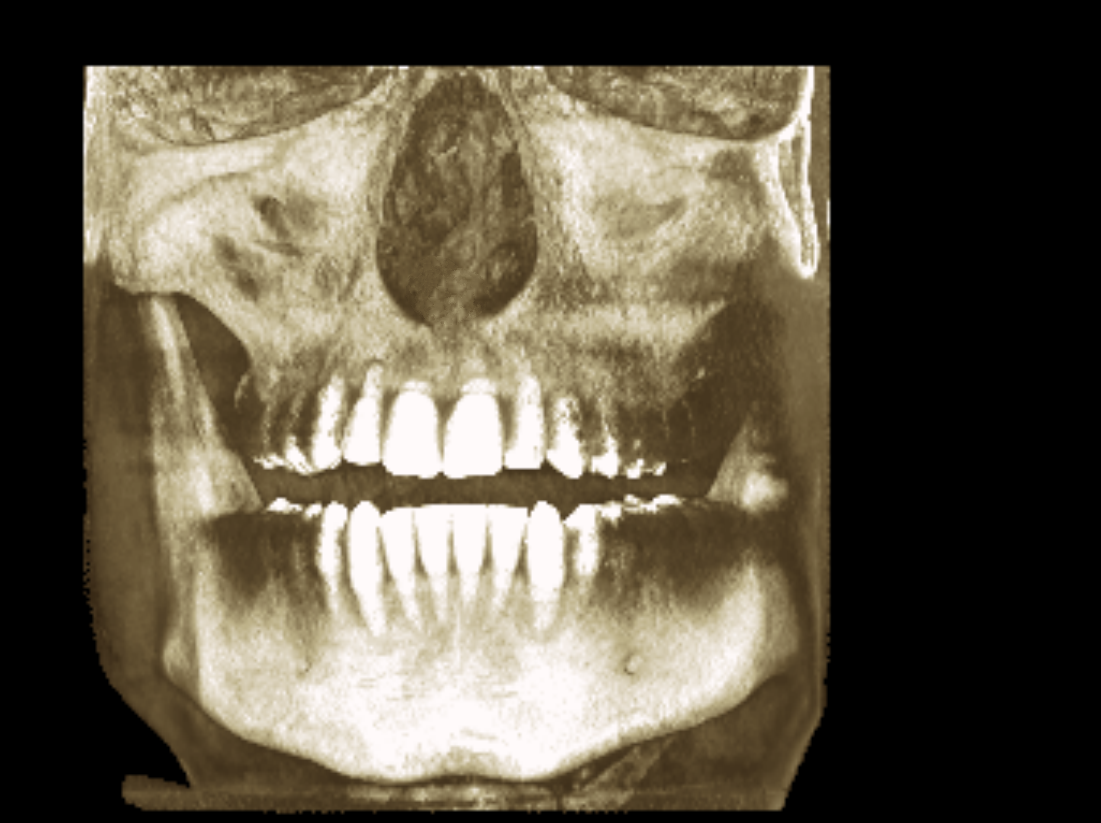

seems to be centered, it's just the alveolar bone playing tricks with you head, your teeth are a lil overcrowded and the "midline" in the teeth has "shifted" (thankfully because of the xray you can see that with braces a clear aligner or even a toothborne expander you could fix your overcrowded lower teeth and move the "mid-line" to the right spot, your occlusion doesn't follow the "guide lines" of the bones also I notice that the upper jaw seems to be inlign with the "midline"(teeth and the base of the nasal cavity as you can see in the image)

The alveolar bone in the upper jaw seems to be shifted

seems like you chew on the left side and you prob have had or will have TMJ issues or masseter cramps, still that puts us at the last point: your occlusion has problems you need to see you can align the teeth without expanding or expanding first and then aligning